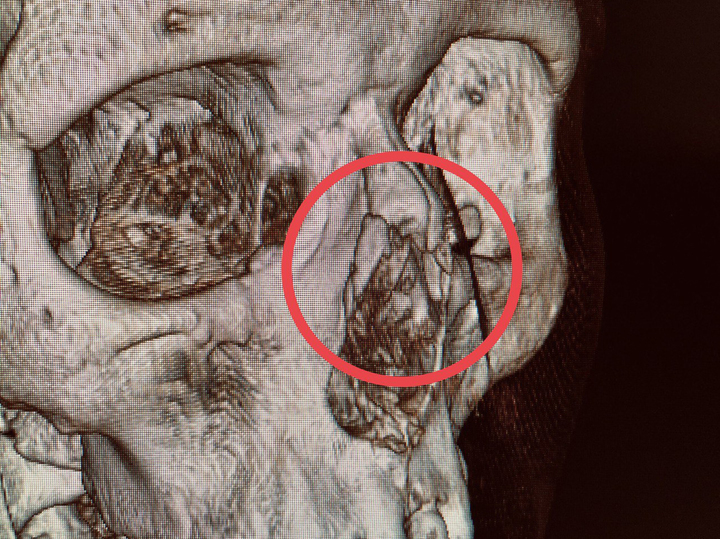

Пострадавшую отвели на рентген. Диагностика выявила перелом костей носа со смещением отломков. Врачам пришлось потрудиться, чтобы привести нос в порядок. Под местным обезболиванием хирурги вправили смещенные отломки и зафиксировали их в правильном положении. Через десять дней после травмы специалисты отметили, что орган не только нормально функционирует, но и внешне выглядит прекрасно.